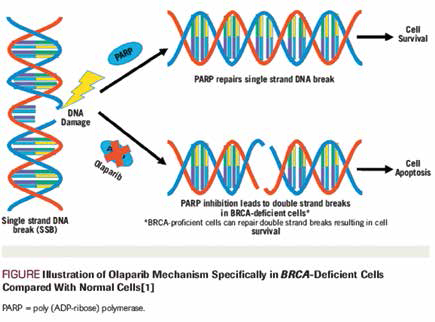

英国研究者Mateo等报告,治疗携带DDR基因异常的转移性去势抵抗性前列腺癌患者时,Olaparib有抗瘤活性,该结果支持在此类患者的临床实践中开展基因分层。(Lancet Oncol.201…